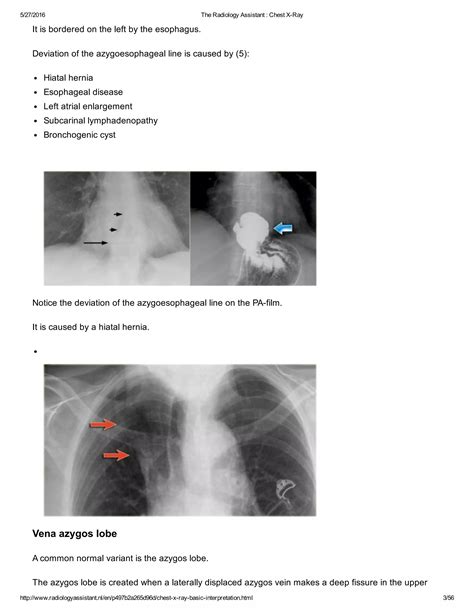

The hallmark of the Vena Azygos Lobe on a chest radiograph is a characteristic curvilinear density. Because of its unique formation, it is easily identifiable if one knows what to look for. Clinicians and radiologists typically identify the following features:

• The Azygos Fissure Line: A thin, convex line extending from the apex of the right lung toward the hilum.

• The Azygos Point (or Teardrop): A dense, teardrop-shaped opacity at the inferior end of the fissure line. This represents the cross-section of the misplaced azygos vein itself.

• Location: Always found in the right upper lobe.

While standard chest X-rays are usually sufficient for diagnosis, computed tomography (CT) provides a definitive view. On a CT scan, the Vena Azygos Lobe is clearly demonstrated as an isolated pleural-lined segment of lung tissue separated from the rest of the right upper lobe by the azygos fissure.